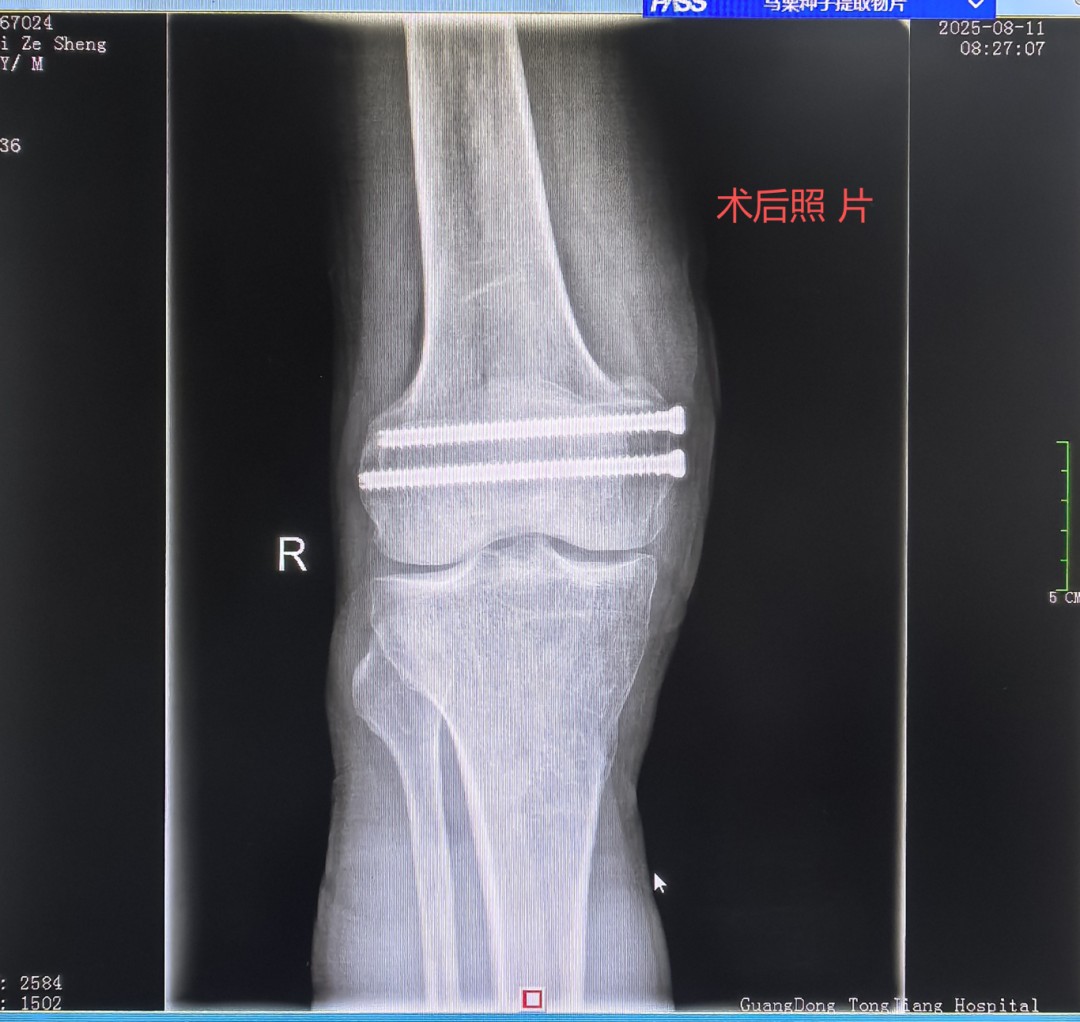

秋意初显,阳光和煦。9月20日骨二科医生办公室迎来一位熟悉的“家人”这位刚出院一个月的梅先生。他扶拐步履稳健,笑容满面,与入院时因车祸受伤平车推入院时判若两人。他此行的目的,一是回来复查,二是要亲手将一封情真意切的感谢信交到我们医务人员手中,以此表达对骨二科全体医护人员最诚挚的谢意。 时间回溯到2025年08月06日, 梅先生上班刚到单位门口车祸不慎致“右股骨髁间骨折、右膝半月板损伤”同事即送急诊后收治入我科,这次意外损伤不仅给梅先生不管是生活上还是愈合恢复都是一种困扰,伤筋动骨100天对一个家庭生活的支柱躺下来带来的困扰与焦虑也是不想而知,这175高的中年男子被这意外变得六神无主快崩溃了。 得知梅先生的意外和焦虑,骨二科罗永立主任带领团队迅速行动。马上制定精准的手术方案,于8月9日为梅先生行:右股骨髁间骨折切开复位内固定术 三分医治七分护理,徐凌峰护长带领护理团队秉承“以患者为中心”针对梅先生制定优质服务理念,从术后无痛管理、到早期快速康复功能锻炼指导,每一个环节都凝聚着我们的专业水平与人文关怀。在医、护、患三方的共同努力下,梅先生恢复神速,根据梅先生的情况术后第一天可以摇高床头坐起来,第二天可以扶床下地站,第三天扶拐下地活动。术后复查照片结果骨折对位良好,住院仅用了13天。梅先生就可以出院回家休养,这么快速可以回家?可以扶拐下地?再不是伤筋动骨100天的长期卧床等康复。家人同事与邻居看见梅先生从受伤到回家到可以下地活动,简单的生活能自理。真的让梅先生与家人象梦境一样。难以想象,便事件告诉他们这就是我们同江医院的精湛医术及优质护理。 当梅先生与古医生约好一个月要回院复查时,就带上出院后就写好的感谢信一起送到古医生手里,看见他扶拐稳健的步伐和灿烂的笑容。一封感纸短情长,字里行间充满感激的簿张却是对骨二科团队医术医德的赞誉和对护理工作的深切感激。这封信,不仅是对我们过往工作的肯定,更是鞭策我们不断前行的动力。 梅先生短短康复之旅,就是骨二科团队践行“敬佑生命、救死扶伤、甘于奉献、大爱无疆”职业精神的一个缩影。精湛的医术是根,优质的护理是叶,而患者的信任与康复,则是我们共同培育出的最甜美的果实。未来将继续用专业、爱心和担当,为每一位患者的健康保驾护航,书写更多温暖生命的奇迹! 图:患者感谢信